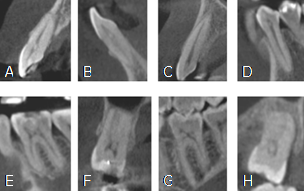

La presencia de calcificación era una imagen hiperdensa oval o redonda dentro de la pulpa dental (Figura 1). También se analizó de acuerdo con la presencia de caries, restauración (superficial: hasta un tercio de la dentina afectada, media: de un tercio a dos tercios de la dentina afectada, profunda: dos tercios de toda la dentina afectada, pero sin exposición pulpar), tipo de pieza dentaria, grupo dentario. La edad y sexo se obtuvieron de la base datos del centro tomográfico.

Calcificaciones en diferentes cortes TCHC (A) incisivo central superior, (B) incisivo lateral inferior, (C) canino superior, (D) premolar inferior, (E) primera molar inferior, (G) segunda molar inferior, (H) tercera molar superior en vistas sagitales y (F) primera molar superior en corte coronal.